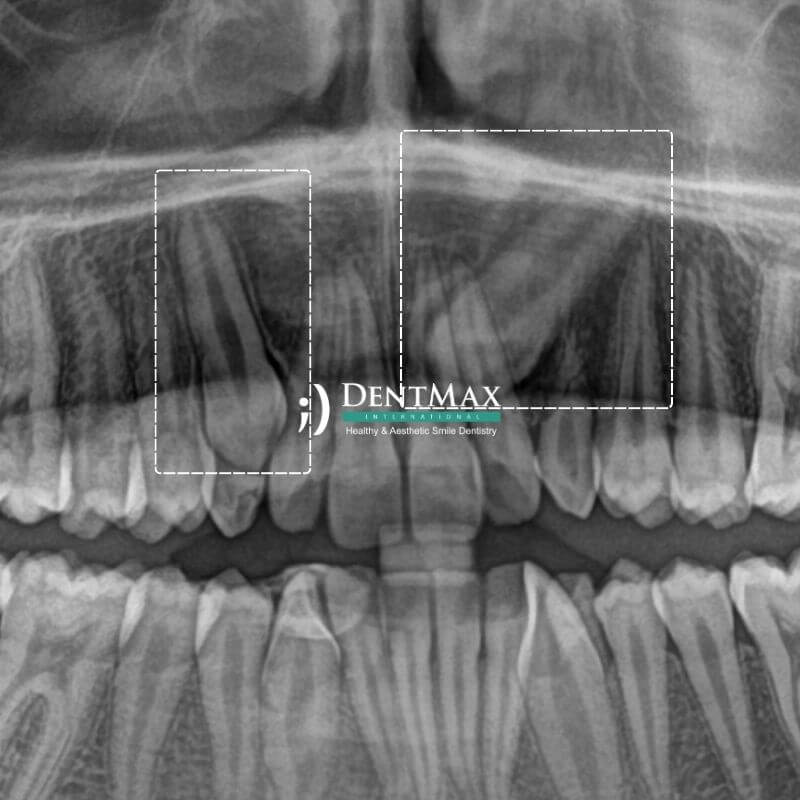

• Kök kanal tedavisi sonucunda rengi koyulaşan dişler.

• Yaş, devitalizasyon (canlılığını kaybetmiş dişler), florozis, tetrasiklin antibiyotik kullanımına bağlı renk değişimi yaşayan dişler.